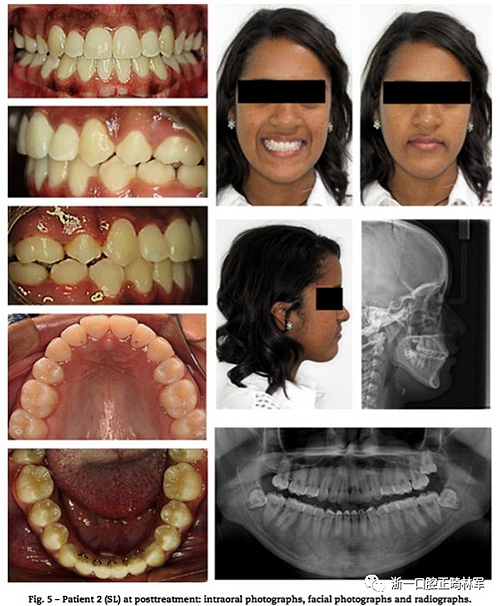

患者2使用0.022的Roth自鎖托槽,弓絲序列為0.014,0.016,0.018熱激活NiTi絲;0.018,0.02,及0.018×0.025的不銹鋼絲,治療初期拔除前磨牙,隨后在側切牙和尖牙間使用NiTi開口彈簧打開間隙后用NiTi絲排齊,排齊整平時間用了14個月,后期使用橡皮筋牽引微調,整個階段維持24個月(圖3,圖5)。

兩例下頜均使用3×3固定保持器,上頜使用改良Hawley保持器。在患者1和2治療過程比較顯示如圖6。頭影測量圖的疊加中證實了極大的相似性(圖7),治療前治療后和保持后的差異見圖8,9。